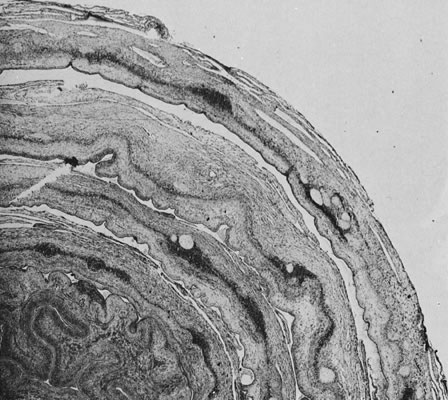

The laying down of a fibrinoid layer at the maternal/placental interface is a standard process of normal pregnancy. This layer of Nitabuch's fibrin is progressively laid down throughout gestation, leading to, at term, a smooth plane of cleavage for the delivering placenta. Even this “normal” amount of coagulation in the basal plate has been proposed to occur as a result of maternal/placental immunologic interactions. The authors also identified increased basal plate coagulation in cases of pregnancy compromise believed to be of immunologic origin.159 This increase in basal coagulation results in a thick band of basal plate fibrin/fibrinoid, with up to several layers of entrapped and variably well-preserved basal villi, often with focal villitis. We have often seen a subjective increase in basal cytotrophoblasts in such cases, a finding that may be reflected in the observations by Redline and Patterson123 of increased basal cytotrophoblast in preeclampsia. We speculate that although an intrinsic trophoblast defect cannot be ruled out, trophoblast invasion is impaired by the markedly abnormal basal matrix. It is also possible that deposition of Nitabuch's fibrin occurs in response to basal cytotrophoblast. Much further work is required to dissect the causal pathways of defective placentation and pregnancy compromise. A highly unusual placental lesion, maternal floor infarction (Fig. 18), shares the histologic features of uteroplacental and decidual “sparing” and intervillous fibrin/fibrinoid but is much more massive, generally involving 80% to 95% of the villous parenchyma. We have seen potential intermediate lesions in the central basal plate: irregularly increased basal fibrin/fibrinoid and 5 to 15 layers of entrapped necrotic villi in cases of recurrent pregnancy loss. Perhaps maternal floor infarction, a rare lesion recognized to recur in subsequent pregnancies, is an extreme example of a coagulopathy initiated by pathologic maternal/placental interactions in the basal plate. Milder forms of this lesion (in which 5 to 20-plus villi are entrapped in encroaching parabasal fibrin/fibrinoid) are not uncommonly found in serial pregnancies from women with recurrent pregnancy loss. Anecdotally, this lesion may not be modified by maternal aspirin/heparin therapy.

Fig. 18. Maternal floor infarct associated with intrauterine demise at 26 weeks.